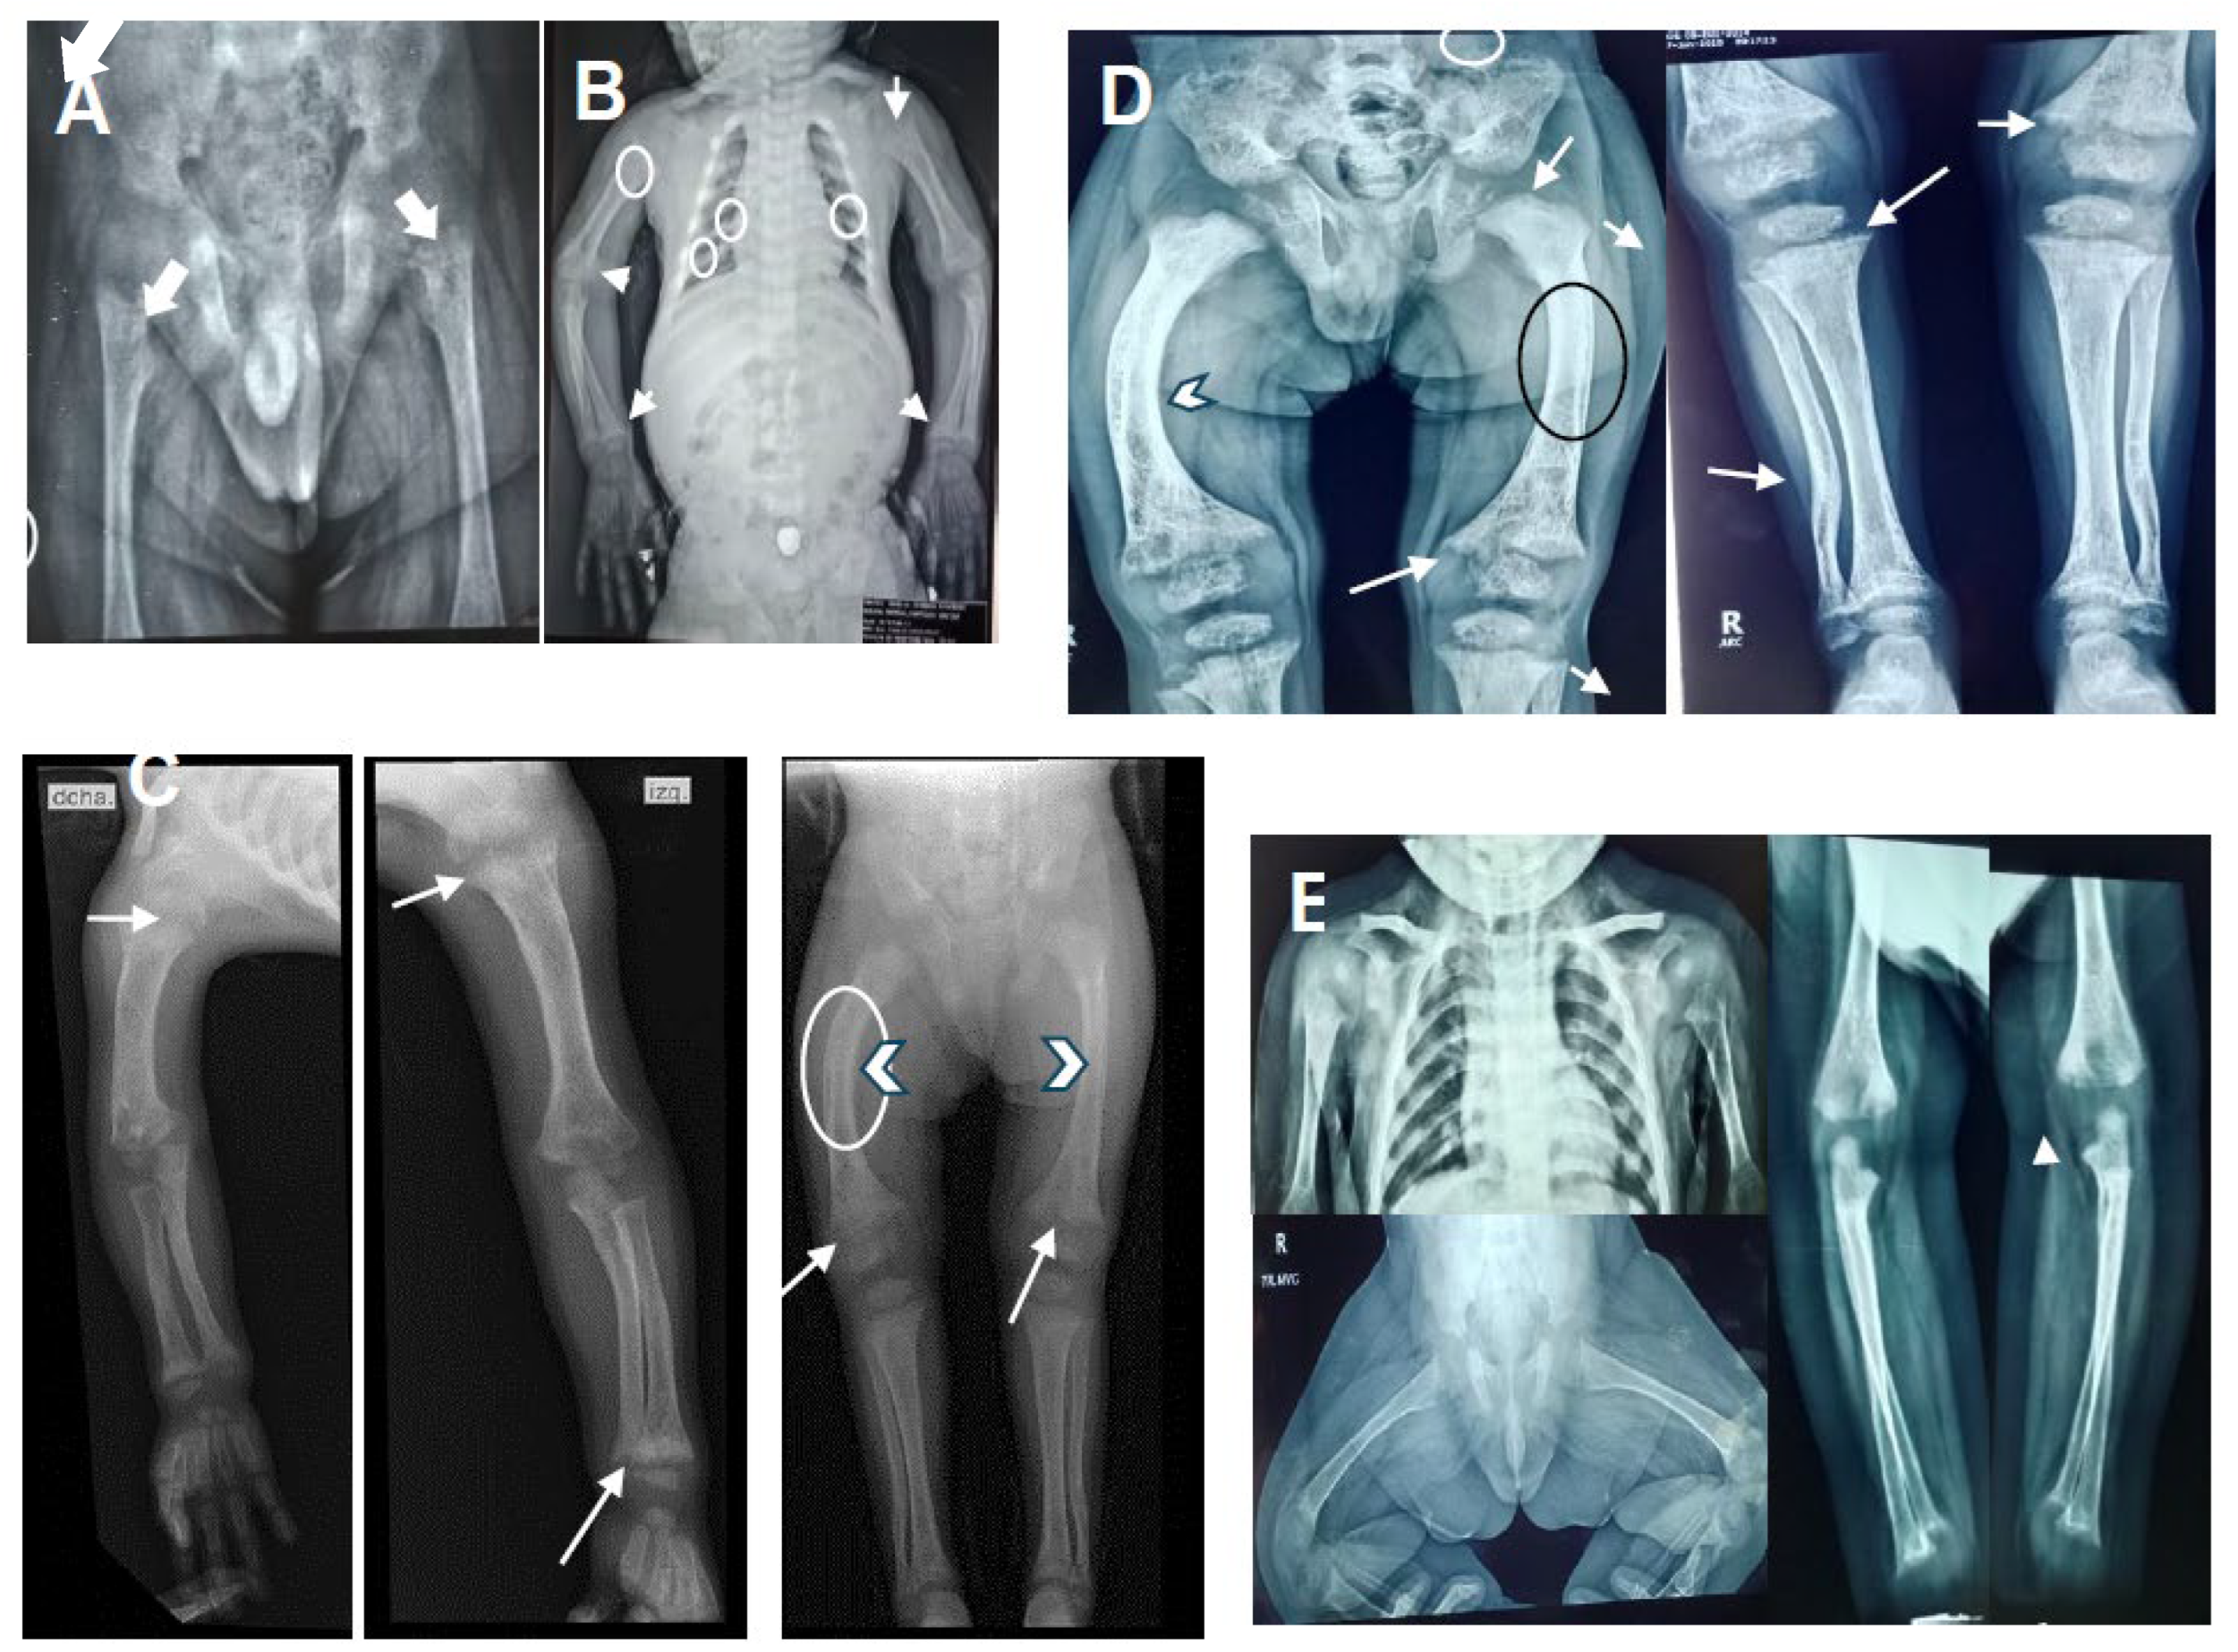

Physical examination at 6 years-10 months of age, had a weight of 19,250 kg (10th centile), length of 103 cm (<3rd centile; -5.6 SD [standard deviation]), and OFC of 53.5 cm (75th centile). He had frontal bossing, midface hypoplasia, blue-grayish sclera (Figure 2B), small teeth, slight pectum carinatum, a widening right wrist and bilateral genu varum. Café aut lait greater than 1 cm were observed on the thorax and abdomen. External genitalia were Tanner I. X-rays showed a thickened short rib, a bilateral cystic femoral head, shortening of long bones with decreased density, irregular widening of the metaphysis, and curved diaphysis (Figure 1A-D).

Initial biochemical study at 13 months of age showed hypophosphatemia, normocalcemia and normal 25(OH)D3 levels, a diagnosis of hypophosphatemic rickets was suspected. More study at 14 months showed high levels of PTH and ALP, while, the 1,25(OH)2D3 was low. Thus, a diagnosis of vitamin D-dependent rickets was made. The proband began treatment with calcitriol at a dose of 0.5 μg/day and phosphate supplementation at a standard dose. After 2 months of treatment (16 months old), phosphorus and 1,25(OH)2D3 parameters returned to normal levels, calcium was low, while PTH and ALP remained high, calcium supplementation was added at dose of 500 mg/day. The genetic study at 32 months old confirmed the VDDR1A diagnostic, the biochemical parameters showed normal calcium, phosphorus and 1,25(OH)2D3; PTH and ALP remained high, calcitriol dose was changed to 1.5 μg/day. At 67 months old, PTH normalized, ALP was observed in mild high levels until the last evaluation (82 months of old). His stature is short with curved tibias. Renal tubular acidosis was ruled out in view of negative history of polyuria and normal pH in blood gas. The abdominal ultrasound and echocardiogram were normal. Biochemical parameters and radiographic changes of the proband before and after calcitriol treatment are shown in Table 1 and Figure 1A-D, respectively.

The proband’s brother, a 3-year-old male, is the second child of healthy parents, aged 28 and 34 years at delivery. Pregnancy was uneventful without prenatal exposure to teratogens or maternal illness. He was born by vaginal delivery at 37 weeks of gestation with a weight of 3,135 g (25–10th centile), length of 52 cm (75th centile), and OFC of 34 cm (25–10th centile). Apgar’s scores were 81, 95, without special neonatal management. On last physical examination at 3-year-old, he had a weight of 16 kg (75–50th percentile), length of 90 cm (25-10th percentile; -1.5 SD), and OFC of 51 cm (50th centile). His motor-intellectual development has been normal. Sanger sequencing at 2 months old was positive for the same mutation as his brother, he was treated with calcitriol dose of 1.0 μg/day from the third month old. After 16 months post-treatment ALP remained slightly above of upper limit, whereas, the calcium, phosphorus, 1,25(OH)2D3, and PTH levels were normal (Table 1). Renal tubular acidosis was ruled out. Radiographic images at one year of age were observed with minimal changes (Figure 1E). At 3-year-old his growth is normal, without fracture or body deformities The renal ultrasound, thyroid profile, expanded metabolic screening were normal.

Doses of calcitriol ranging from 0.5 to 2 μg/day or 0.008 to 0.40 μg/kg/day have been used to treatment of VDDR1A (11,16,19). Our proband was treated with calcitriol at doses of 0.5-1.5 μg/day, after 53 months of follow-up all biochemical parameters normalized, except for ALP that remained slightly high (Table 1), similar behavior was seen in the proband’s brother after 19-month follow-up, this indicative yet of pathological activity. However, in our proband radiographic images showed partial improvement (Figure 1A, B,C,D), clinically remained with short stature and a curved tibia. In the proband´s brother the imaging studies showed mild changes of cupping and fraying without widening (Figure 1E), the stature is normal (-1.5 SD), without deformities or nephrocalcinosis. Our proband had good compliance with his treatment, the partial response to treatment could be explained by the delay in management and the presence of truncated variants as previously observed, where adults or children older than 12 years with truncating variant and delayed treatment were seen to be more severe than those without this variant type, which led to permanent short stature and deformities (1,11). Another study of 12 children that presented truncating by the frameshift variant in at least one allele, were observed with delayed growth when were treated late and did not have correct compliance (21). In the treatment of a 13-month-old girl, a good biochemical response at 10 months post-treatment was observed, however she presented multiple fractures but growth or deformity data were not reported (7). In our case 2, the diagnosis at 3 moths and early treatment helped a good biochemical response, limitation of rickets without delayed growth, fractures or deformities. Therefore, according to this and previous studies the truncated variants suggest give a more severe phenotype, but a diagnosis and early treatment with a correct compliance and an adequate dose are important factors that must be taken care of for a better health prognosis in the patients with VDDR1A.

Figure 1. Shows X-rays of the proband and his brother before and after calcitriol treatment. (A) The proband at 10-month-old with discrete cupping and widened metaphysis (white arrows). (B) Shows the proband at 2 year and 6-month-old (18 months post-treatment) with wide anterior rib ridge, irregularity of costal bodies associated with osteopenia (small white circles), humerus with diffuse osteopenia (big white circle), increased amplitude of the growth plate, at the level of the radius and ulna with frayed, cupped metaphysis and membranous ossification (white arrows) consistent with rickets. (C) Proband at the 3-year-old and (D) at 4 year-6-moths-old shows partial recoveries with diaphyseal slope (white arrowhead), cupping, widening and fraying at metaphysis of long bones (white arrows). Qualitative improvement in bone density is observed (black circle). (E) Shows X-ray of the proband’s brother at 9 months post- treatment with minimal changes in the bone density, cupping or fraying without widening in the metaphysis of humerus, femur, radius and ulna (white arrows) are observed.